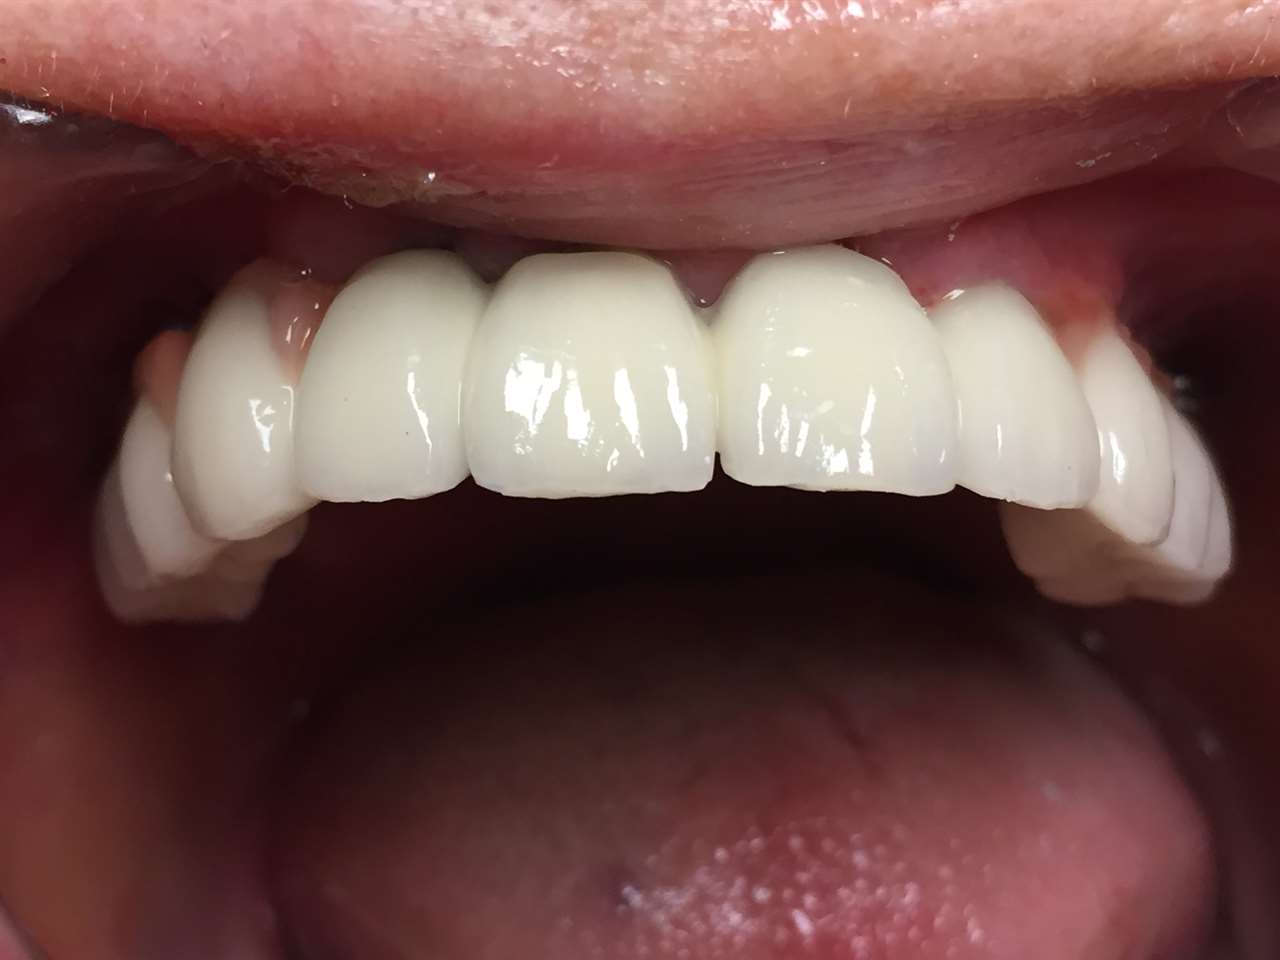

A régóta fennálló foghiány és a mozgó fogak miatt a páciens nem tudott jól rágni és harapni, illetve mosolyogni sem mert már jó ideje. A leggyorsabb és a legesztétikusabb megoldás az ilyen esetekre az IHDE azonnal terhelhető implantátumok behelyezése, és az azokra rögtön elkészített porcelán koronák elkészítése.

A teljes munka - az implantáció, a végleges koronák elkészítése - 5 munkanapot vett igénybe.

A mozgó, törött fogakon álló hidat a fogakkal együtt eltávolítottuk.

A fogak helyére, és a stratégiailag jó csontállományú hátsó területre azonnal behelyezett implantátumokra 3 nap múlva elkészítettük az esztétikus, azonnal terhelhető ideiglenes hidat.